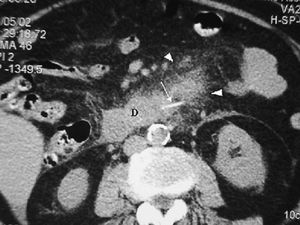

El duodeno puede lesionarse por procedimientos endoscópicos y/o quirúrgicos, al igual que por cuerpos extraños ingeridos (fig. 4). La apariencia radiológica de las lesiones será similar a las producidas por traumatismos externos, reflejando un engrosamiento de pared, alteración de la grasa periduodenal y líquido y/o aire periduodenal o en retroperitoneo en caso de rotura11.

Fig. 4--Perforación duodenal por espina de pescado. (A) Ecografía donde se observa una estructura lineal hiperecogénica (flechas) que sale del duodeno (D). (B) En el estudio de tomografía computarizada se identifica como material hiperdenso (flecha) que corresponde a la espina de pescado, con reacción de la grasa adyacente (puntas de flecha) y líquido en espacio pararrenal anterior derecho.